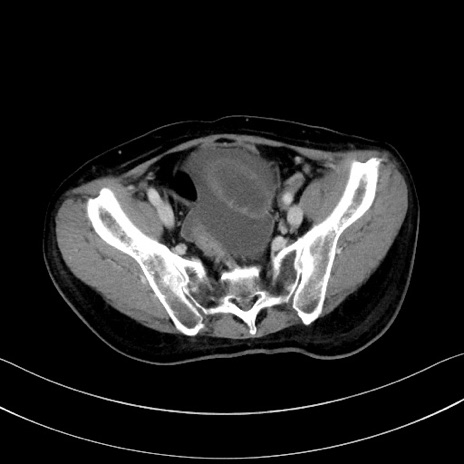

症例28(横断像)

【症例】60歳代男性

【主訴】嘔吐

【現病歴】胃癌にて胃全摘後。食思不振が悪化し、夜中に嘔吐することがある。

【既往歴】胃癌、胃全摘、脾摘、胆摘後

【データ】WBC 5900、CRP 10.56